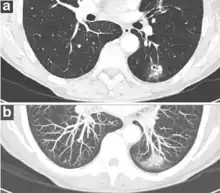

Part solid nodule.[9]

Ground glass opacity nodule.[9]